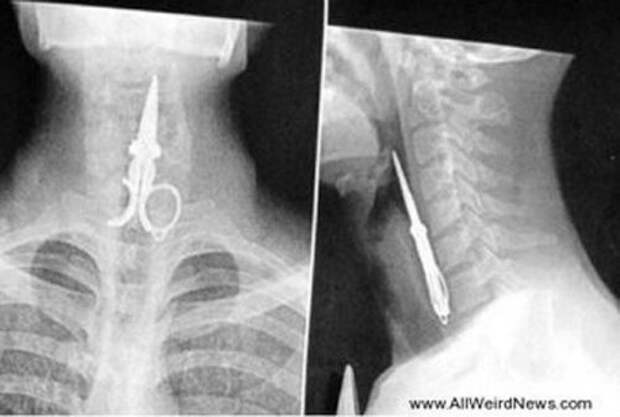

Этот парень ковырялся в зубах при помощи ножниц, но начал смеяться и ножницы провалились в горло. Он выжил и пострадал не сильно!

Рентгеновский снимок ножниц, оставленных внутри желудка Пэта Скиннера (Pat Skinner) из Хёрствилля (Hurstvlle) во время операции в больнице Святого Георгия (St George Hospital), Сидней.